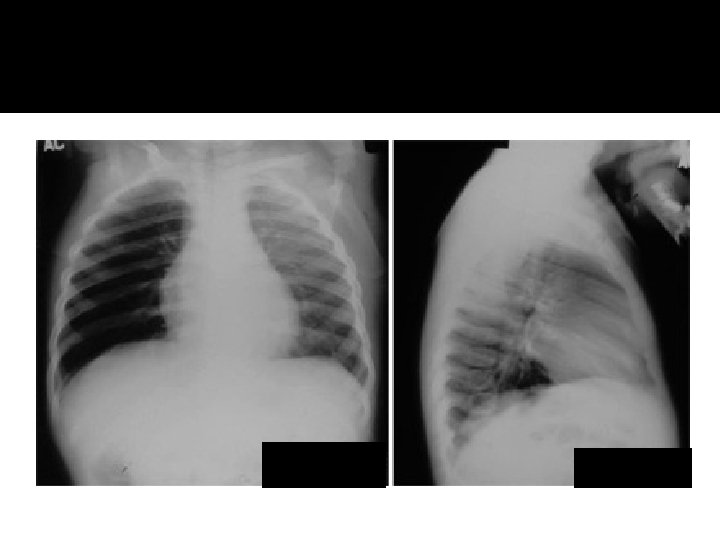

Atelectasis RML

Pneumonia lingula

Atelecasis RML